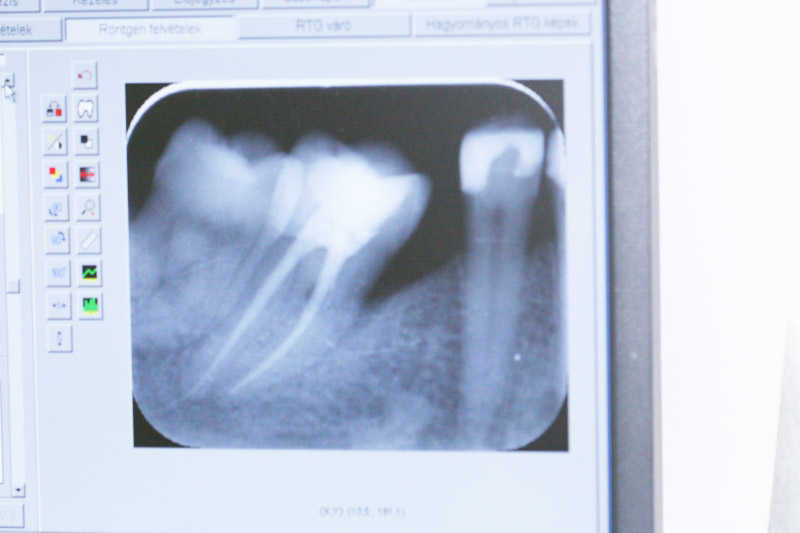

Az elkészült gyökértömés kontroll röntgenfelvétele